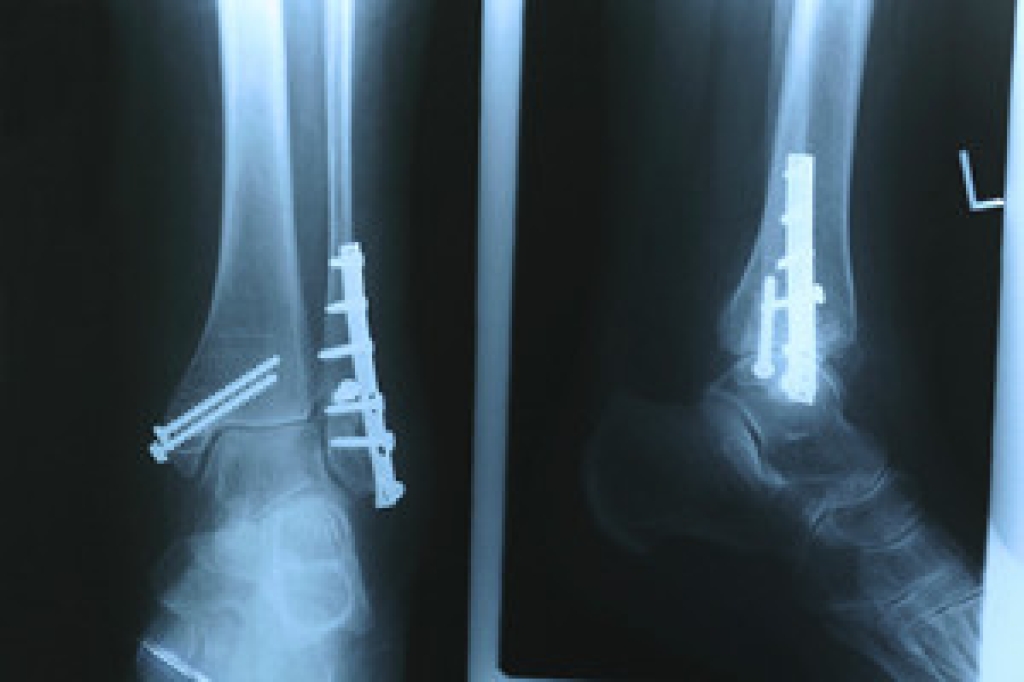

Diabetes affects millions of people every year. The condition can damage blood vessels in many parts of the body, especially the feet. Because of this, taking care of your feet is essential if you have diabetes, and having a podiatrist help monitor your foot health is highly recommended.